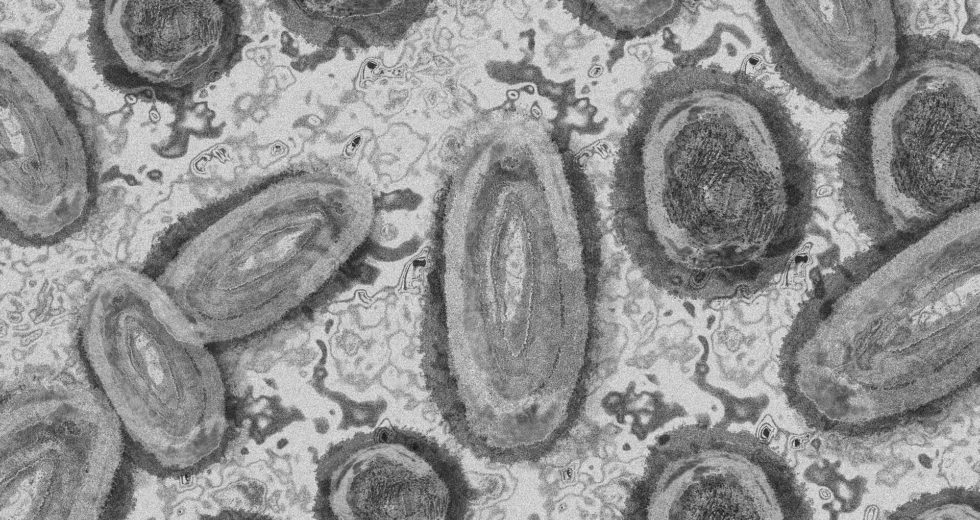

The monkeypox virus seems to be mutating much faster than scientists have ever expected. This and more has been made…

The World Health Organization has announced that “Monkeypox” will be renamed due to it being a discriminatory term. This piece…